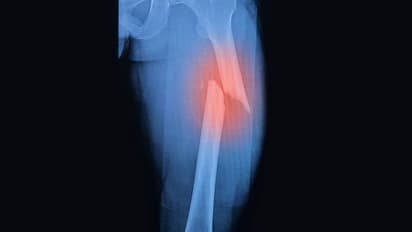

ಮೂಳೆ ಮುರಿತದ ಬಗ್ಗೆ ವೈದ್ಯರು ಸಂಶೋಧನೆ ನಡೆಸಿದ್ದು, ಸಾಮಾನ್ಯವಾಗಿ ವಯಸ್ಸಾದವರಿಗೆ ಹಾಗೂ ಕಾಯಿಲೆ ಇರುವರು ಮೂಳೆ ನೋವಿನಿಂದ ಬಳಲುತ್ತಾರೆ. ಈ ಸಮಸ್ಯೆ ವಯಸ್ಕರಲ್ಲಿಯೇ ಏಕೆ ಎಂದು ಪತ್ತೆ ಹಚ್ಚಲು ಸಂಶೋಧನೆ ನಡೆಸಲಾಗಿತ್ತು.

ಯಾವುದೇ ಮೂಳೆಗೆ ಹಾನಿಯಾದರೂ ಮೊದಲೆರಡು ವರ್ಷಗಳು ಎಲುಬಿನ ಸಾಂದ್ರತೆ ಕಡಿಮೆಯಾಗುತ್ತದೆ. ಇದು ಮಂಡಿ ನೋವು, ಭುಜ ನೋವು...ಹೀಗೆ ದೇಹದ ವಿವಿಧ ನೋವಿಗೆ ದಾರಿಗೆ ಮಾಡಿ ಕೊಡುತ್ತದೆ. ಯಾವಾಗಲೋ ತಿಂದ ಏಟು, ಇನ್ಯಾವುದೋ ಸಮಯದಲ್ಲಿ ಮನುಷ್ಯನನ್ನು ಕಾಡುತ್ತದೆ.

ಎಲುಬಿನ ಸಾಂದ್ರತೆ ಕಡಿಯಾಗುವುದರಿಂದ ರಕ್ತದಲ್ಲಿ ಉರಿಯಾಗುತ್ತದೆ. ಚಿಕ್ಕ ಮೂಳೆಗಾಗುವ ಪೆಟ್ಟನ್ನು ಚಿಕಿತ್ಸೆ ಮೂಲಕ ಸರಿಪಡಿಸಬಹುದಾಗಿದ್ದು, ವಯಸ್ಸಾಗುತ್ತಿದ್ದಂತೆ ಅದರ ಸುತ್ತ ಇರುವ ಮೂಳೆ ನೋವೂ ಶುರುವಾಗುತ್ತದೆ.